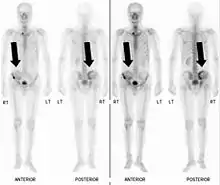

Bone scintigraphy

Also known as a bone scan, bone scintigraphy involves the injection of a small amount of radioactive tracer into the bloodstream. This tracer decays and emits radioactive energy which can be detected by a special camera. The camera produces a black and white image where areas shown as dark black indicate bone damage of some kind. If there is a black spot in the lumbar vertebrae (e.g. L5) this indicates damage and potentially spondylolysis. If this test is positive, a CT scan is usually ordered to confirm spondylolysis.[13]

Commonly known as a CT Scan or CAT scan, this form of imaging is very similar to x-ray technology but produces many more images than an x-ray does. The multiple images produce cross-sectional views not possible with an x-ray. This allows a physician or radiologist to examine the images from many more angles than an x-ray allows. For this reason the CT scan is much more accurate in detecting spondylolysis than an x-ray. Bone scintigraphy combined with CT scan is considered the gold standard which means that it is best at detecting spondylolysis.[13][15]